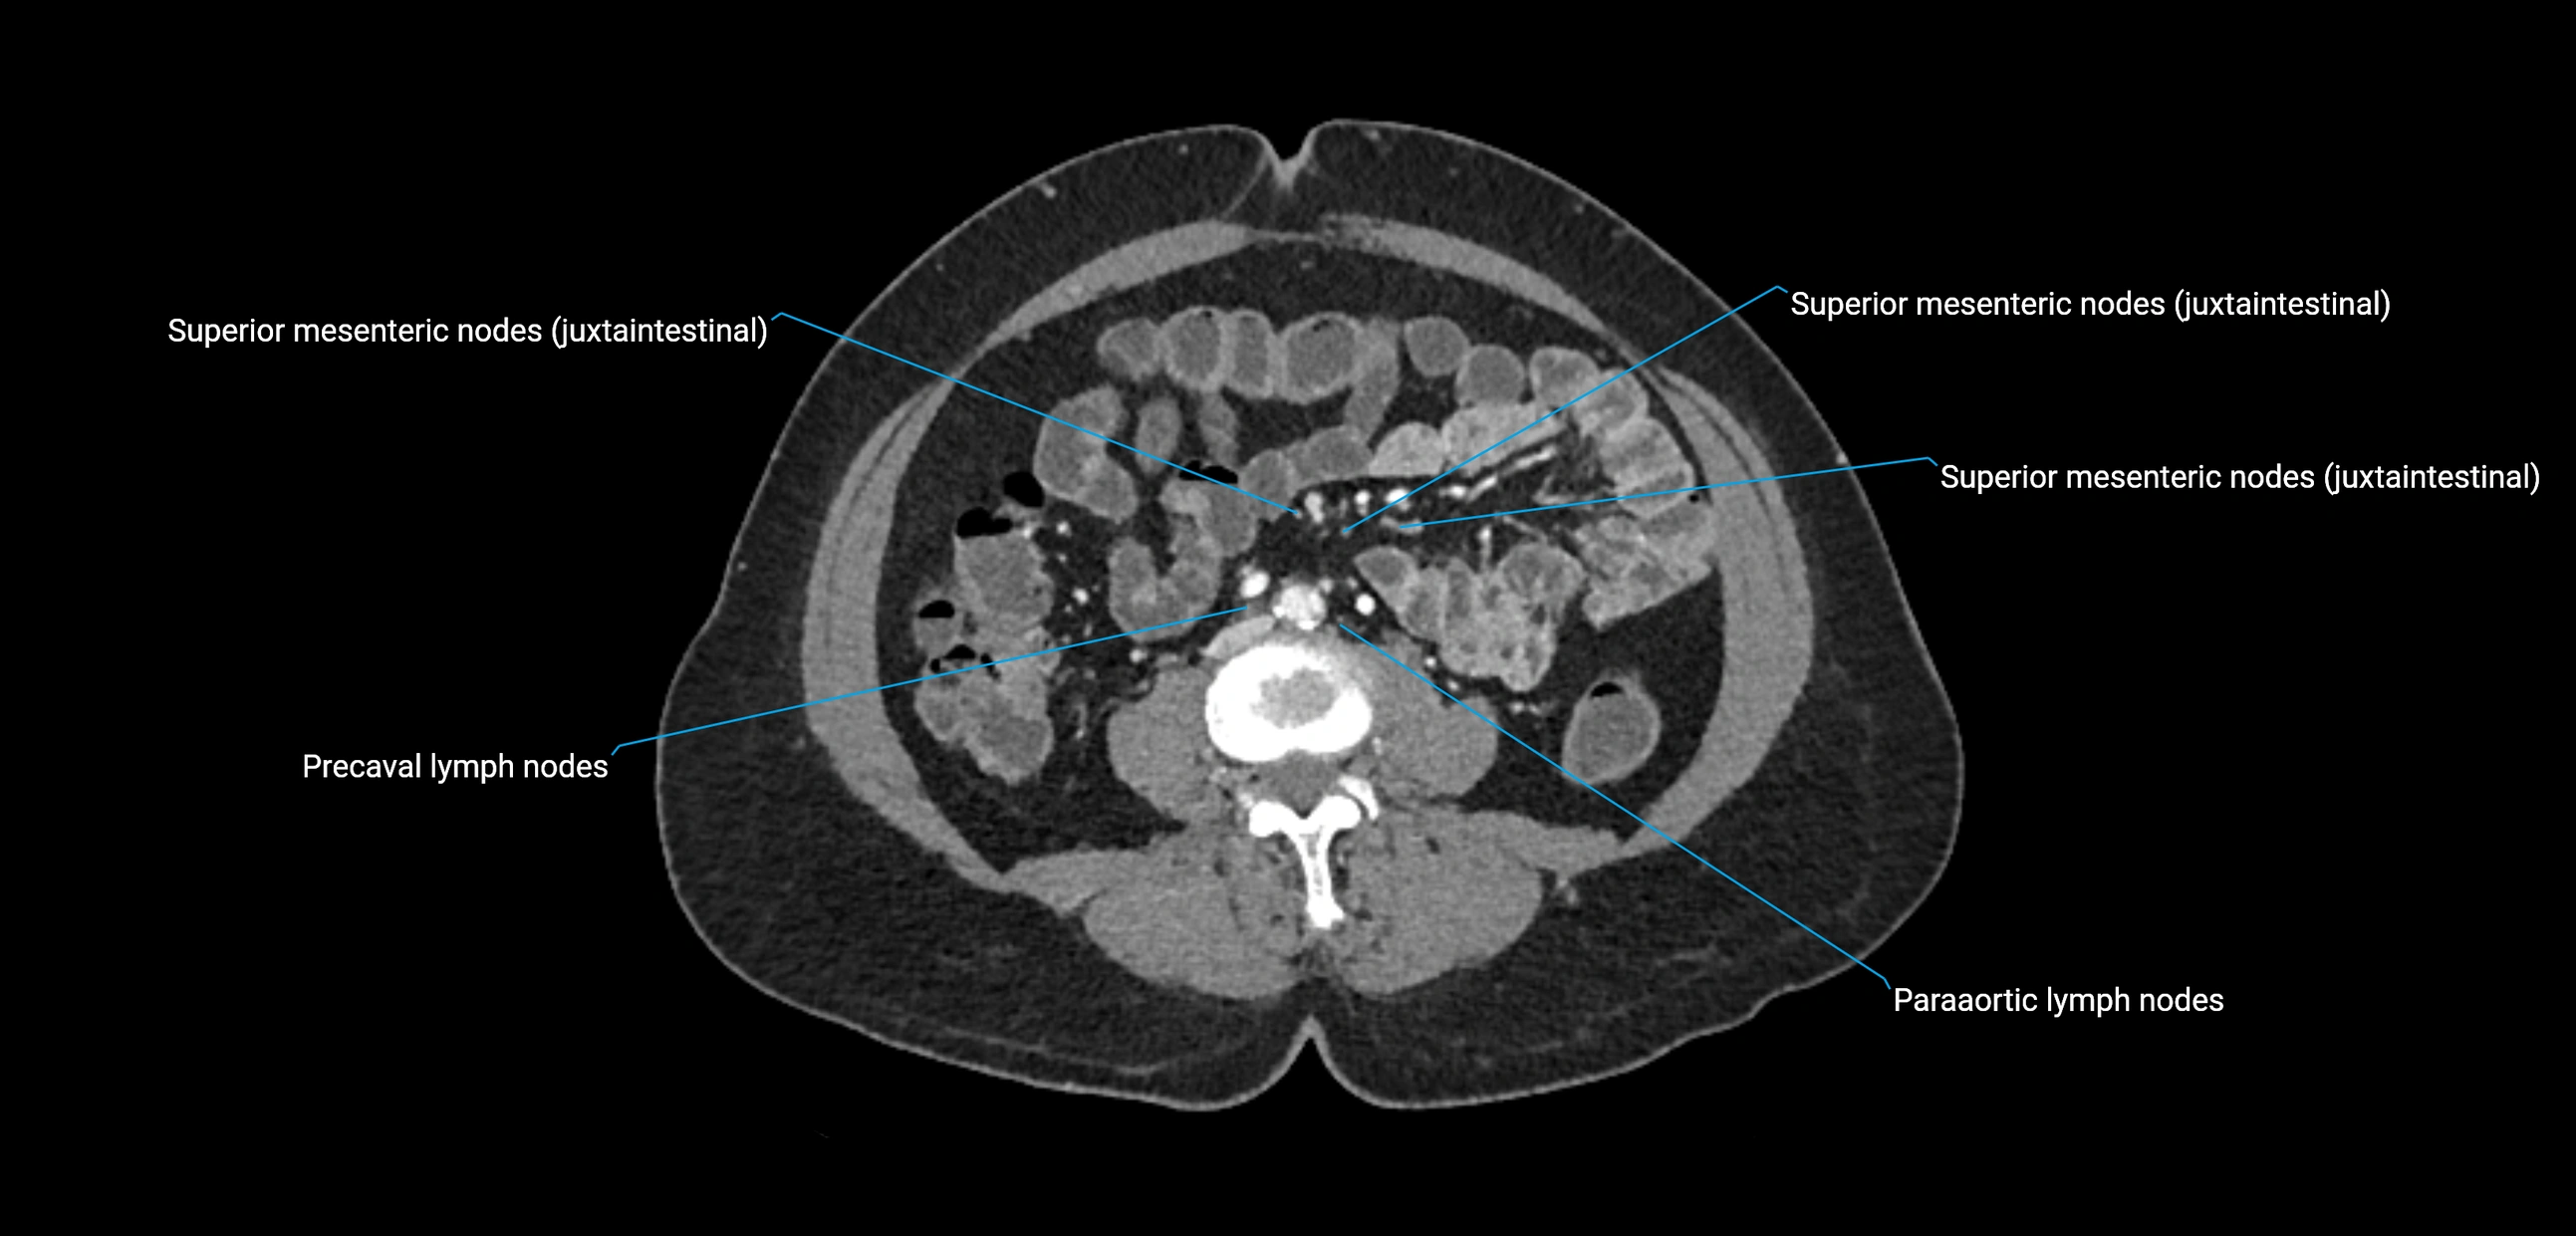

CT Appearance

CT Pre-Contrast:

• Nodes appear as soft-tissue density nodules adjacent to the aorta and IVC

• Calcification may be seen in chronic infections (e.g., tuberculosis)

CT Post-Contrast:

• Normal nodes enhance homogeneously

• Malignant nodes may show heterogeneous enhancement, central necrosis, or conglomerate formation

• Size >1 cm short axis is suspicious, though morphology and distribution are equally important